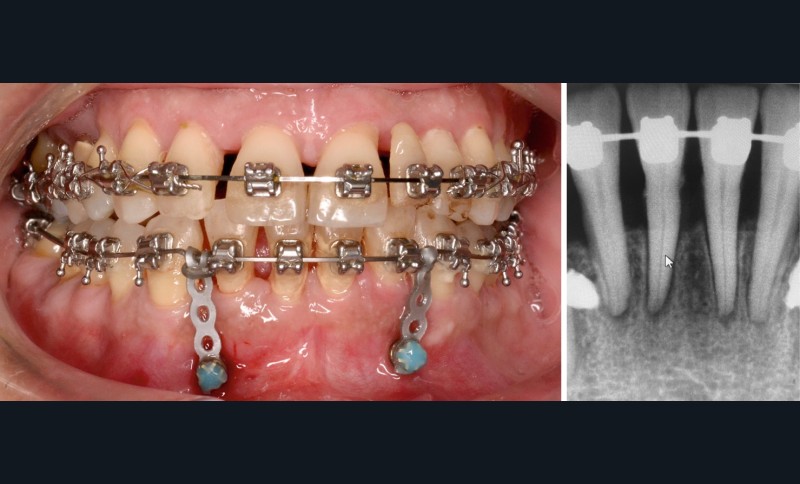

En raison de l’ancrage dentaire postérieur mandibulaire très limité, il est décidé d’utiliser des ancrages osseux pour l’ingression du bloc incisivo-canin mandibulaire, afin de niveler l’arcade et de recréer le surplomb nécessaire à la fermeture des diastèmes maxillaires. Deux minivis d’ancrage sont positionnées entre les dents 32/33 et 42/43, après réalisation d’un examen CBCT localisé sur l’arcade mandibulaire (fig. 7 et 8). Ces minivis antérieures ont été rapidement déposées, en raison de leur mobilité et de la gêne importante de la patiente liée au positionnement très apical du fait de l’alvéolyse.

Des minivis d’ancrage sont alors positionnées entre les dents 34/35 et 44/45 (fig. 9). Un sectionnel d’ingression antérieur (acier .018x.025) est fixé sur celles-ci, tout en passant par des tubes en croix situés entre les prémolaires afin d’éviter le dévissage des minivis. L’ingression est réalisée via des ligatures reliant l’arc orthodontique principal (TMA .018x.025 avec boucles double-delta) au sectionnel, selon une direction permettant l’ingression tout en limitant la composante de vestibulo-version. Du stripping mandibulaire a été réalisé de mésial de 33 à mésial de 43 afin de corriger l’indice de Bolton.